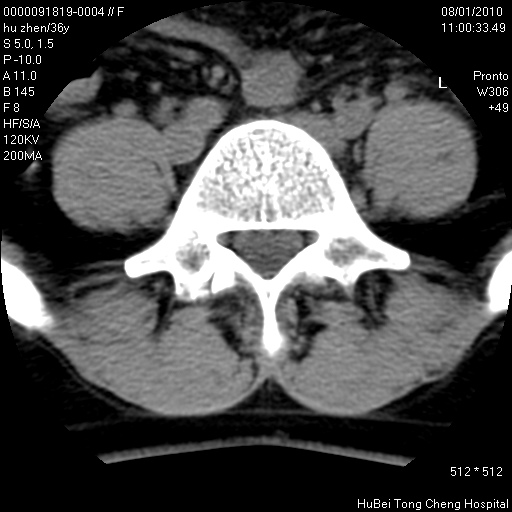

患者 女,36岁。右侧腰腿痛半月余。腰骶椎mr平扫偶然发现骶椎异常信号。

临床诊断:1)腰椎间盘突出症。2)骶椎肿瘤性病变?

骶椎ct平扫(层厚、层距均为5mm),图像如下:

考虑s1骨纤维异常增殖症。

骨良性病变、成骨细胞瘤